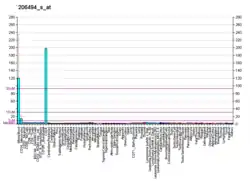

| ITGA2B |

| Aliases | ITGA2B, BDPLT16, BDPLT2, CD41, CD41B, GP2B, GPIIb, GT, GTA, HPA3, PPP1R93, integrin subunit alpha 2b, GT1 |